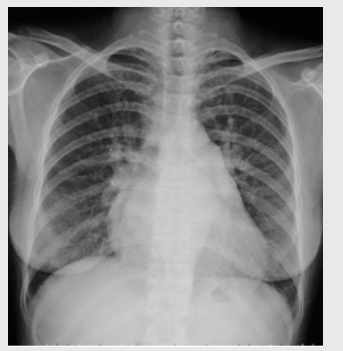

01卷-4.根據(jù)下圖請做出正確診斷

A.右側(cè)肺炎

B.兩下肺炎

C.右下肺肺癌

D.正常胸片